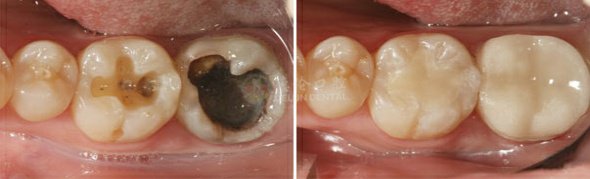

3. 根管治疗

适应症:☆深度龋齿 ☆牙髓坏死 ☆急/慢性牙髓炎 ☆根尖周炎 ☆牙髓外漏

自我诊断:突发性或遇冷热刺激而疼痛;夜晚疼痛升级,不能入睡;牙疼导致面峡部肿胀疼痛使咬合无力,甚至不能正常进食。

治疗疗法:传统根管治疗